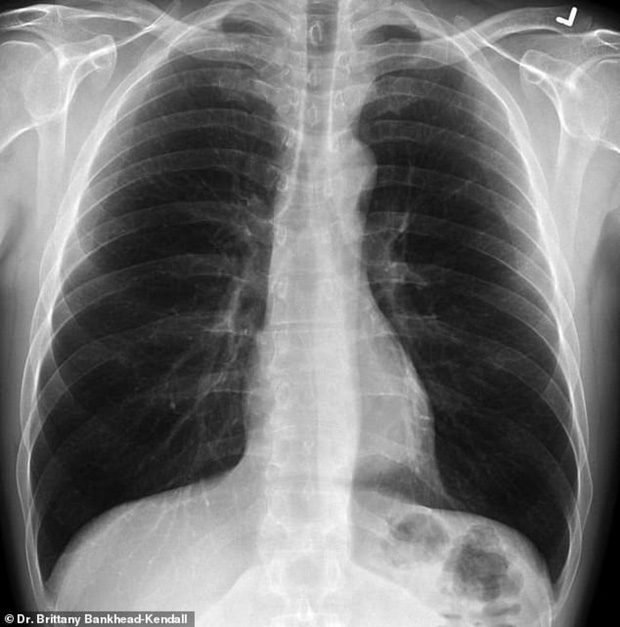

Bác sĩ phẫu thuật Brittany Bankhead-Kendall ở Trung tâm Khoa học Sức khỏe Đại học Kỹ thuật Texas (Mỹ) mới đây trưng ra 3 tấm phim chụp X-quang: Một của bệnh nhân khỏe mạnh, một của người hút thuốc, và một của bệnh nhân Covid-19.

Phim của người khỏe mạnh có nhiều khoảng đen, cho thấy họ có thể hít vào đủ lượng oxy cần thiết. Phim chụp phổi người hút thuốc thì có nhiều khoảng mờ, còn của bệnh nhân Covid-19 thì gần như trắng xóa.

Những khoảng mờ trên phim chụp phổi thường là chỉ dấu của dịch lỏng, vi khuẩn, hoặc tổn thương và vết sẹo.

Bác sĩ Kendall đánh giá, phổi của các bệnh nhân trải qua Covid-19 tệ hại hơn bất cứ người nghiện thuốc lá nào mà bà từng biết.